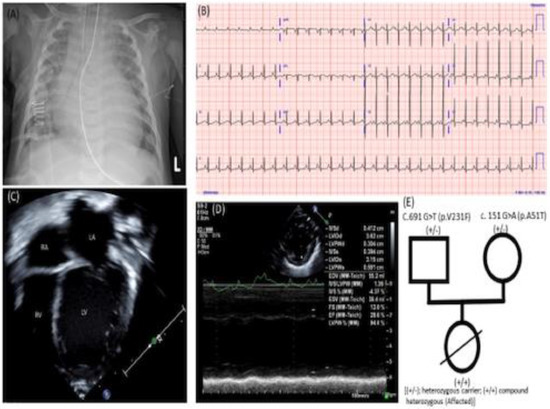

:1. Case Report